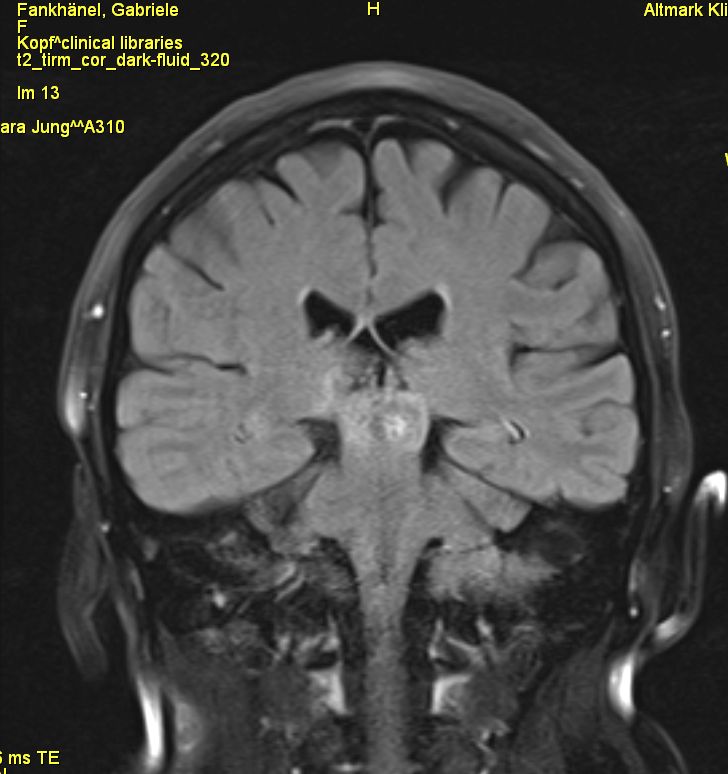

Vierhügelplatte 66-jährige Frau mit Sehstörungen, Ptose rechts mehr als links, Gehörverschlechterung und Gleichgewichtsstörungen. Stereotaktische Biopsie: Astrozytom Grad 3 (Grad unsicher).